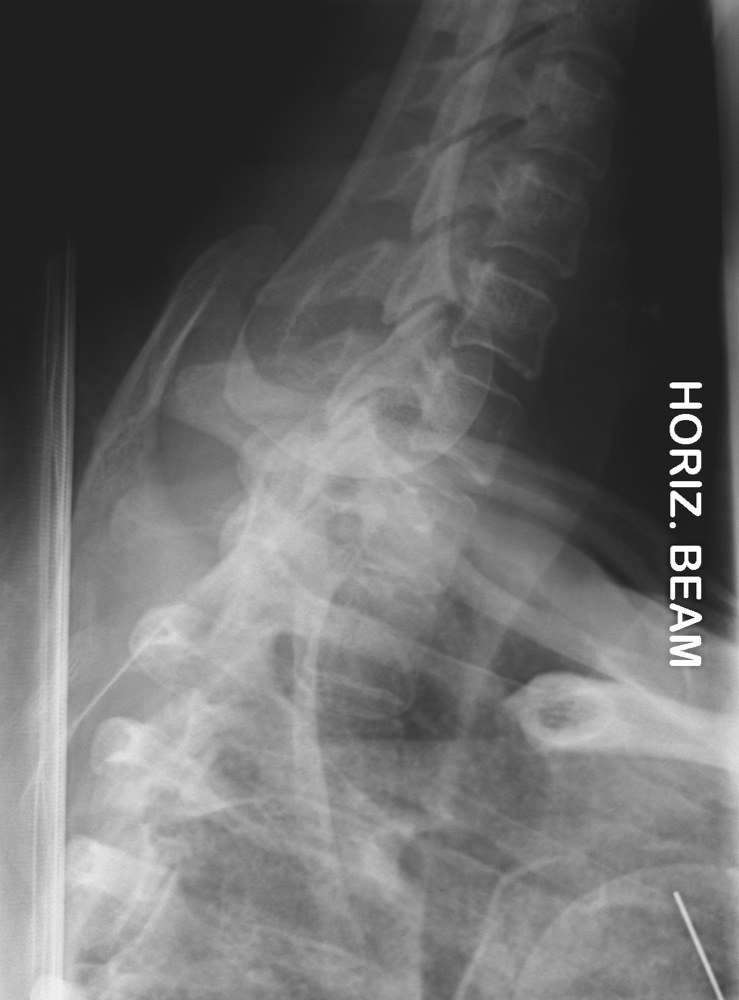

Excellent Swimmer's view. Adequate visualisation of C7T1 junction, C7 Swimmers X-Ray It is usually the humeral. swimmer's views taken following inadequate lateral cervical spine radiographs in trauma patients were. If you are struggling to see down to the level of c7/t1, a fourth “ swimmer’s view ” can be requested. the swimmers view is all about getting the humeral heads projected clear of the cervical spine anatomy. Swimmers X-Ray.